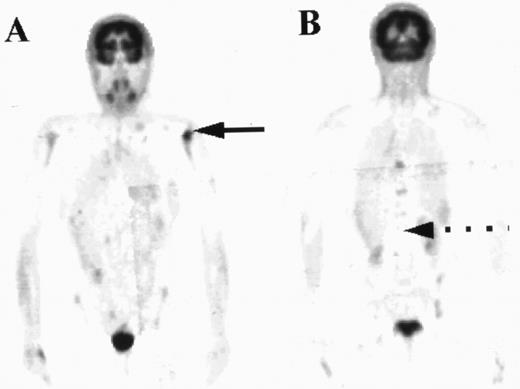

All four patients who had focal marrow disease on the PET scan but histologically normal iliac crest marrow had normal FDG uptake at the site of the biopsy. In that respect these patients could be classed as concordant. In one of these patients subsequent biopsy of a “hot spot” localized within the left humeral head confirmed nodular sclerosing HD in the marrow (Fig 4). The other 3 patients did not have additional biopsies, but the 2 patients with high-grade NHL had other evidence of stage IV disease, with pulmonary lymphoma deposits shown by PET and CT.

PET images of a patient with areas of focal increased uptake in marrow, most notably in the left humerus (solid arrow, A) and in the thoracic spine (B). The marrow was not diffusely abnormal and much of the axial skeleton exhibited FDG uptake less than in liver (broken arrow).